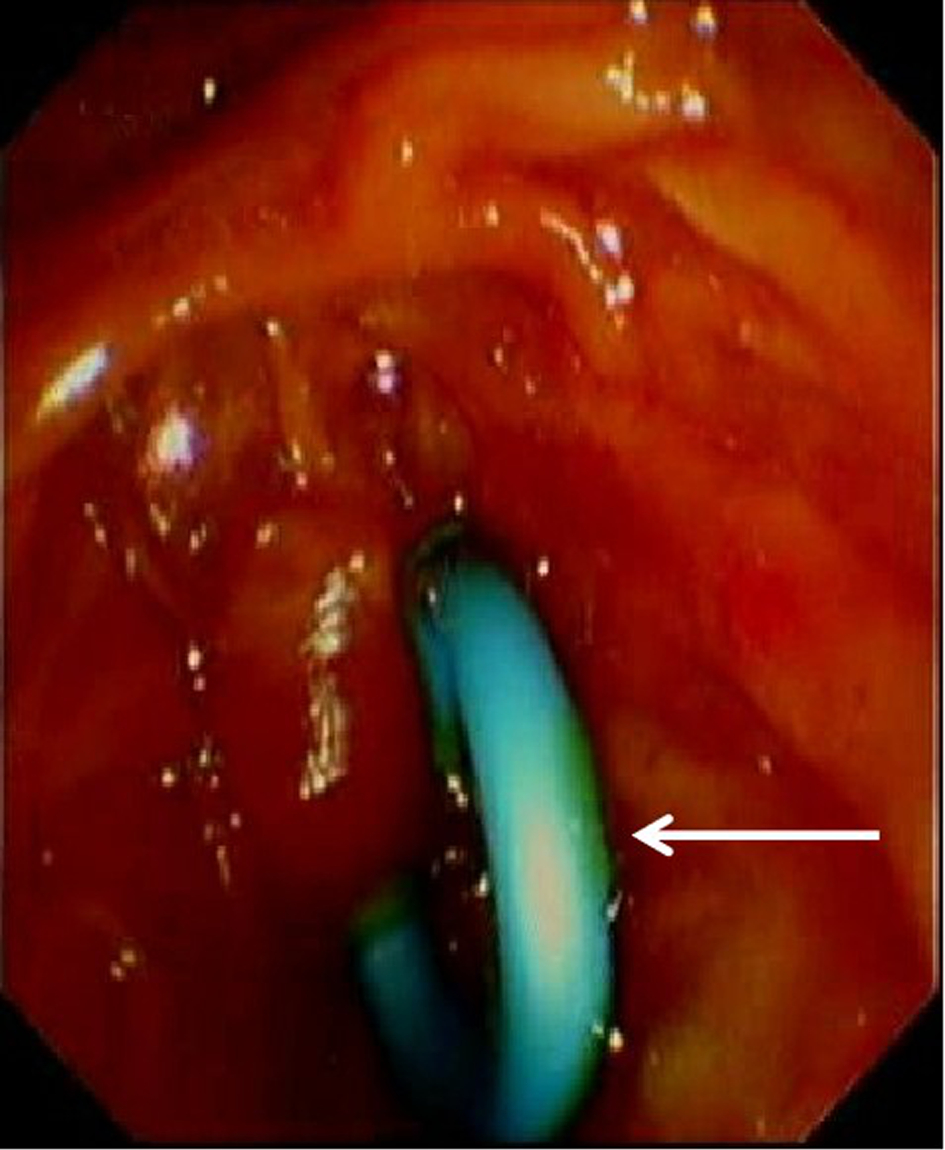

Safety and efficacy of modified pancreatic duct stent in biliary drainage after complete bile duct stone removal by endoscopic retrograde cholangiopancreatography

Jialin LI, Likun REN, Xun RAN, Shaoxuan XIA, Yutong ZHOU, Xin HUANG, Min HAN

2023, 39(8): 1911-1918. DOI: 10.3969/j.issn.1001-5256.2023.08.021

Abstract(1487) HTML (620) PDF (2008KB)(63)

Abstract:

Objective  To investigate the clinical application value of modified 7Fr pancreatic duct plastic stent in biliary drainage.  Methods  Clinical data were collected from 121 patients with choledocholithiasis who underwent endoscopic retrograde cholangiopancreatography (ERCP) lithotomy and biliary drainage in Department of Hepatobiliary Surgery, The Affiliated Hospital of Guizhou Medical University, from April 2021 to June 2022, and according to the method for postoperative biliary drainage, they were divided into modified stent group with 59 patients and nasobiliary drainage group with 60 patients. The patients in the modified stent group received drainage with the modified 7Fr pancreatic duct plastic stent, and those in the nasobiliary drainage group received nasobiliary drainage. A retrospective analysis was performed for their clinical data, and stent dislodgement was observed for the modified stent group. The two groups were compared in terms of clinical outcome, postoperative comfort, and postoperative complications. The independent-samples t test was used for comparison of normally distributed continuous data between groups, and the Mann-Whitney U test was used for comparison of non-normally distributed continuous data between groups; the chi-square test was used for comparison of categorical data between groups.  Results  Both groups achieved a stone clearance rate of 100%. There were significant differences between the two groups in the length of postoperative hospital stay and the total length of hospital stay (t=-3.997 and 2.317, both P < 0.05). After treatment, both groups had significant reductions in total bilirubin (TBil), direct bilirubin (DBil), indirect bilirubin (IBil), alkaline phosphatase (ALP), aspartate aminotransferase (AST), and gamma-glutamyl transpeptidase (all P < 0.05), and there were no significant differences between the two groups in the changes in TBil, DBil, IBil, ALP, alanine aminotransferase, and AST after treatment (all P>0.05). Also, no significant differences were observed between the two groups in the changes in biochemical parameters after treatment (all P>0.05). There were significant differences between the two groups in comfort score within 24 hours after surgery and the time to first eating and drinking after surgery (t=2.001, 3.579, and 4.604, all P < 0.05). There were no significant differences in complications between the two groups (all P>0.05). In the modified stent group, the rate of spontaneous stent dislodgement was 83.05%, and there were no complications such as stent occlusion, displacement, rupture, perforation, and infection.  Conclusion  After complete bile duct stone removal by ERCP, biliary drainage using the modified 7Fr pancreatic duct plastic stent has a similar effect to nasobiliary drainage and can shorten the length of postoperative hospital stay, improve postoperative comfort, and accelerate postoperative recovery, with a relatively high spontaneous dislodgement rate. Therefore, it is safe and effective in clinical practice.